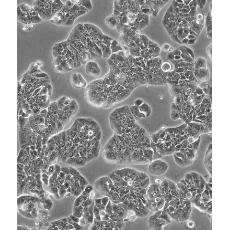

HT-29

中文名稱(chēng) 人結(jié)腸癌細(xì)胞

形態(tài)特征 上皮樣

生長(zhǎng)特性 貼壁生長(zhǎng)

特征特性 該細(xì)胞是1964年由FoghJ用移植培養(yǎng)方法和含15%FBS的F12培養(yǎng)液從原發(fā)性腫瘤分離的。近來(lái),已建株的培養(yǎng)細(xì)胞用含血清的McCoy's5a培養(yǎng)基培養(yǎng)。該細(xì)胞系在裸鼠中成瘤,也能在類(lèi)固醇處理的地鼠中成瘤。該細(xì)胞可合成IgA、CEA、TGFβ結(jié)合蛋白和黏液素;表達(dá)尿激酶受體,但沒(méi)有檢測(cè)到血漿酶原活性;不表達(dá)CD4,但細(xì)胞表面表達(dá)半乳糖神經(jīng)酰胺(HIV的可能替代受體)。該細(xì)胞系癌基因c-myc、K-ras、H-ras、N-ras、Myb、sis、fos陽(yáng)性;p53基因過(guò)表達(dá),并且在273位密碼子處發(fā)